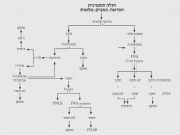

| 11:58, 7 בספטמבר 2012 | TMNgraph412.png (קובץ) |  |

340 קילו־בייטים | Motyk | 1 | |